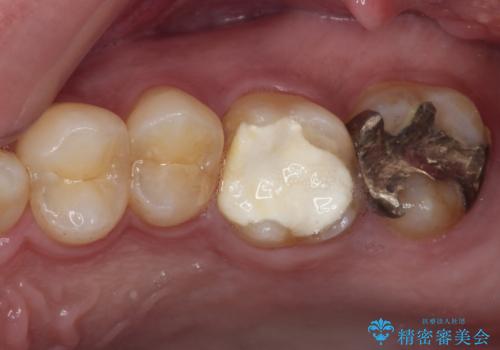

捻れた前歯と銀歯のブリッジを治したい ワイヤー矯正とオールセラミックブリッジ